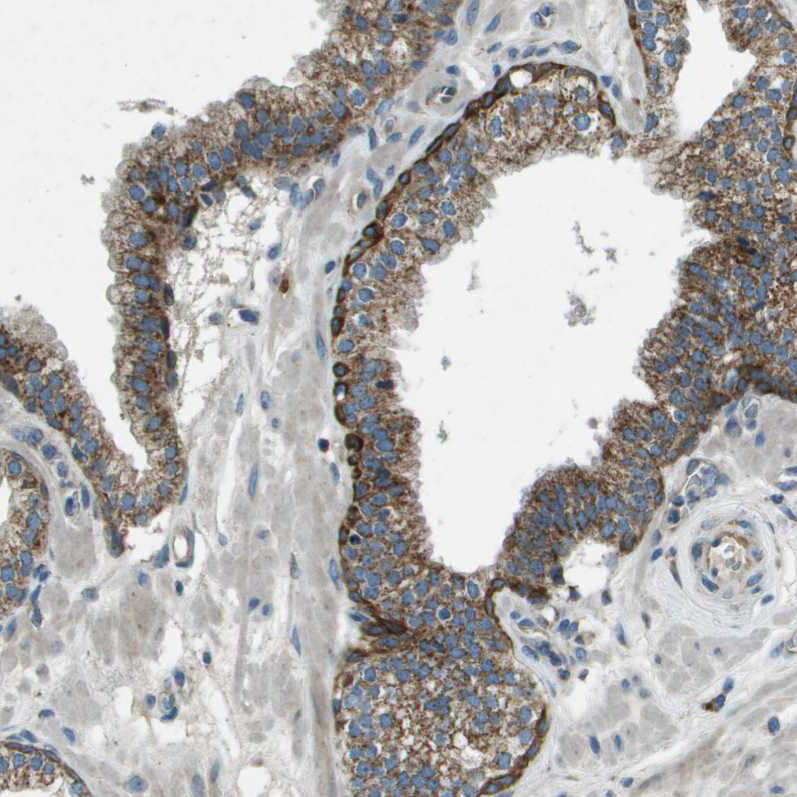

Immunohistochemical staining of human prostate shows moderate to strong granular cytoplasmic positivity in glandular cells.